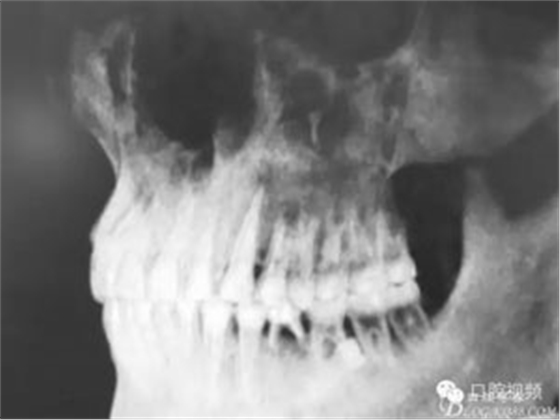

圖15.術(shù)后的全景片資料